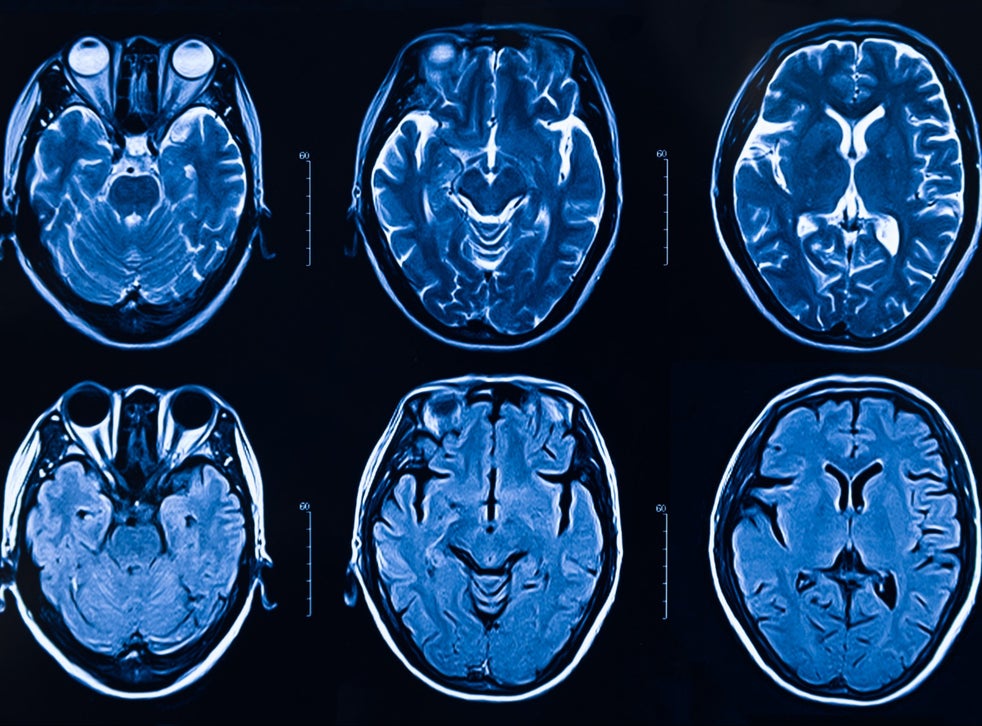

Koronavirusi prek mushkëritë në përgjithësi, por gjithashtu edhe veshkat, mëlçinë dhe enët e gjakut. Prapëseprapë rreth gjysma e pacientëve kanë simptoma neurologjike, përfshirë dhimbjet e kokës, tendosjen dhe hutimin, duke bërë të ditur se virusi mund ta sulmojë edhe trurin.

Letër lexuesit — pse po kërkojmë mbështetjen tuaj KontribuoNjë studim i ri ofron provën e parë të qartë se, në disa njerëz, koronavirusi pushton qelizat e trurit, duke i rrëmbyer ato për të bërë kopje të vetvetes. Virusi duket se edhe e thith të gjithë oksigjenin afër, duke shkaktuar vdekjen e qelizave fqinje.

Është e paqartë se si virusi arrin në tru dhe se sa shpesh nis këtë provim të shkatërrimit. Infektimi i trurit ka të ngjarë të jetë i rrallë, por disa njerëz mund të jenë të ndjeshëm për shkak të prapavijës së tyre gjenetike, një ngarkesë e lartë virale apo arsye të tjera.

Shkencëtarët kanë pasur të mbështeten në skanimet e trurit dhe në simptomat e pacientëve për t’i dalluar efektet në tru, por “nuk është se kemi parë shumë prova që virusi mund ta infektojë trurin, edhe pse e kemi ditur se ka mundësi potenciale”, ka thënë Dr. Michael Zandi, neurolog konsulant në Spitalin Kombëtar për Neurologji dhe Neurokirurgji në Britaninë e Madhe. “Këto të dhëna sigurojnë pak më shumë prova se në fakt mund të infektohet truri”.

Në studimin e tij, Dr. Iwasaki dhe kolegët e saj dokumentuan infektimin e trurit në tri mënyra: në indet e trurit nga një person që ka vdekur nga COVID-19, në një model miu dhe në organoide – grumbujt e qelizave të trurit në një pjatë laboratori duhej ta imitonin strukturën tredimensionale të trurit.